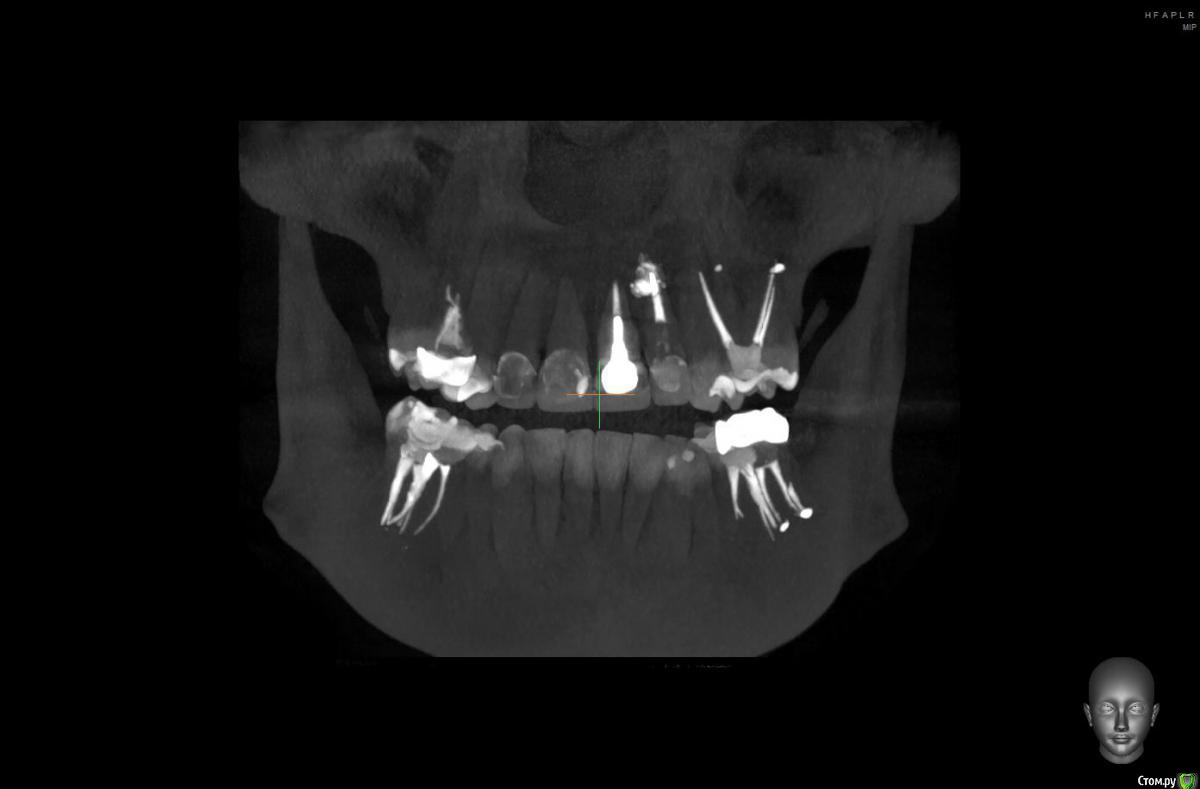

10 лет назад на передних зубах были установлены металлокерам.коронки, на одном из зубов-металлический штифт. (Фото прилагаю)

В 2019 году я решилась поменять коронки, в одном из зубов нашли кисту, долго лечили, вывели лекарство за корень, потом другой врач через микроскоп все пролечил и запломбировал. Решили не делать резекцию, пока не беспокоит.

Ссылку на КТ прилагаю, не знаю откроется или нет.

https://drive.google.com/open?id=1fp042ssCNfvp3B19SGM4TykOPuuaK5gu